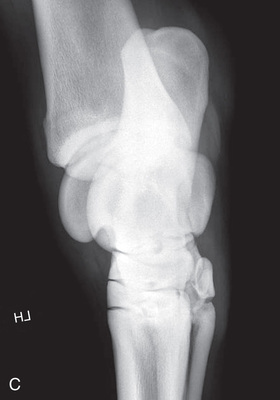

| Stifle | Lateromedial (LM) | Lateral (L) |

| Caudoproximal-craniodistal (CdPr-CrDi) | Caudocranial (CdCr) | |

| Lateral trochlear ridge and medial femoral condyle (stifle) | Caudoproximal 60-degree lateral–craniodistomedial oblique (Cd60L-CrMO) | CdLCrMO |

| Optional stifle | Cranioproximal-caudodistal (CrPr-CdDi) | Craniocaudal (CrCd) |

| Cranioproximal-craniodistal oblique(CrPr-CrDiO) | Skyline patella | |

| Lateromedial flexed (LM) | Flexed lateral (L) |